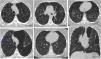

Más datosLa exposición al tabaco guarda una relación reconocida con el desarrollo de enfermedades de la vía aérea y el parénquima pulmonar. Aparte de la enfermedad pulmonar obstructiva crónica, en algunos individuos el humo del tabaco puede desencadenar mecanismos de daño intersticial que resultan en variadas alteraciones patológicas y fibrosis pulmonar. Se ha reconocido un grupo de entidades con una relación causal establecida con el tabaco, que incluye la bronquiolitis respiratoria con enfermedad pulmonar intersticial, la neumonía intersticial descamativa, la histiocitosis de células de Langerhans y la neumonía eosinófila aguda. Aunque el tabaco se considera factor de riesgo, aún es ambiguo su papel e impacto en el desarrollo de la fibrosis pulmonar idiopática, la entidad clínica diferenciada que se ha denominado combinación fibrosis pulmonar y enfisema, y la neumonía intersticial no específica. La definición de la fibrosis intersticial asociada al tabaco es relativamente reciente, con características histológicas diferenciadas. La interconexión probable entre los mecanismos que determinan la inflamación y la fibrosis pulmonar en todos estos procesos referidos se traduce con frecuencia en una superposición de rasgos histológicos, clínicos y radiológicos en el mismo paciente, que en algunos casos puede determinar patrones radiológicos de neumopatía intersticial no clasificables. Por ello es recomendable un abordaje combinado para el diagnóstico, que debe estar basado en la interpretación conjunta de las características histológicas y los hallazgos radiológicos, en el contexto clínico apropiado. Nuestro objetivo se centra en la descripción de los hallazgos radiológicos en la tomografía computarizada de alta resolución, en correlación con las manifestaciones clínicas y las alteraciones histológicas subyacentes al patrón radiológico.

Exposure to smoke is associated with the development of diseases of the airways and lung parenchyma. Apart from chronic obstructive pulmonary disease (COPD), in some individuals, tobacco smoke can also trigger mechanisms of interstitial damage that result in various pathological changes and pulmonary fibrosis. A causal relation has been established between tobacco smoke and a group of entities that includes respiratory bronchiolitis-associated interstitial lung disease (RB-ILD), desquamative interstitial pneumonia (DIP), Langerhans cell histiocytosis (LCH), and acute eosinophilic pneumonia (AEP). Smoking is considered a risk factor for idiopathic pulmonary fibrosis (IPF); however, the role and impact of smoking in the development of this differentiated clinical entity, which has also been called combined pulmonary fibrosis and emphysema (CPFE) as well as nonspecific interstitial pneumonia (NIP), remains to be determined. The definition of smoking-related interstitial fibrosis (SRIF) is relatively recent, with differentiated histological characteristics. The likely interconnection between the mechanisms involved in inflammation and pulmonary fibrosis in all these processes often results in an overlapping of clinical, radiological, and histological features in the same patient that can sometimes lead to radiological patterns of interstitial lung disease that are impossible to classify. For this reason, a combined approach to diagnosis is recommendable. This combined approach should be based on the joint interpretation of the histological and radiological findings while taking the clinical context into consideration. This paper aims to describe the high-resolution computed tomography (HRCT) findings in this group of disease entities in correlation with the clinical manifestations and histological changes underlying the radiological pattern.